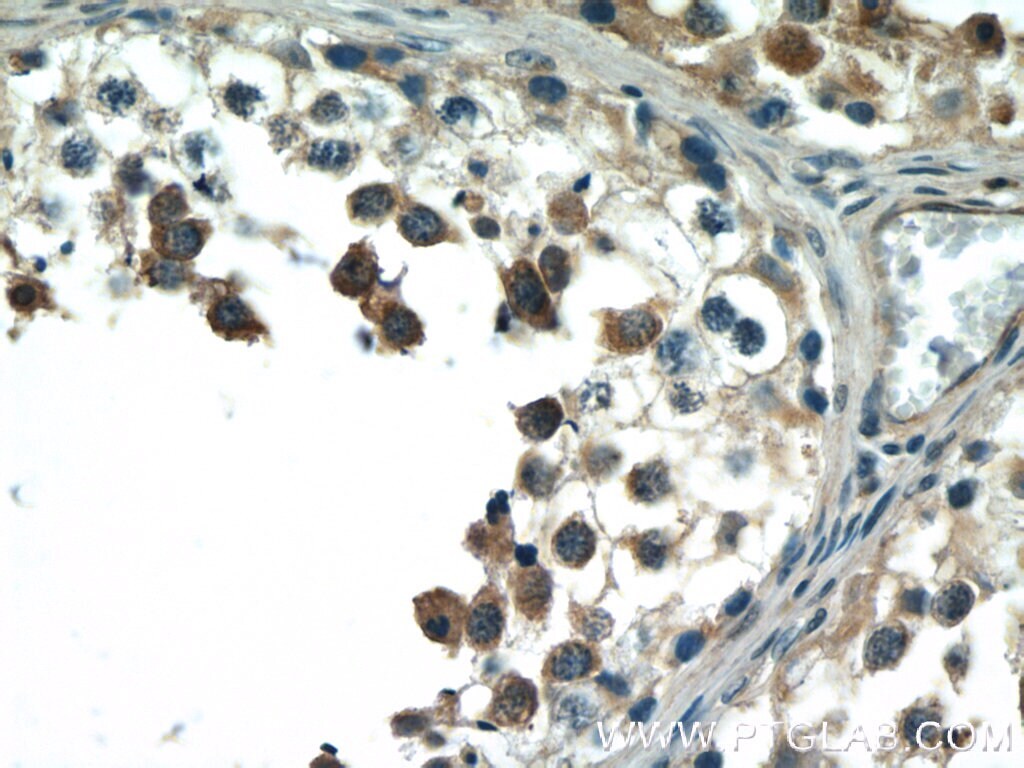

Supportive validation

- Submitted by

- Invitrogen Antibodies (provider)

- Main image

- Experimental details

- Immunohistochemistry of paraffin-embedded human testis tissue slide using 23308-1-AP ( BCMO1 Antibody) at dilution of 1:50 (under 40x lens).